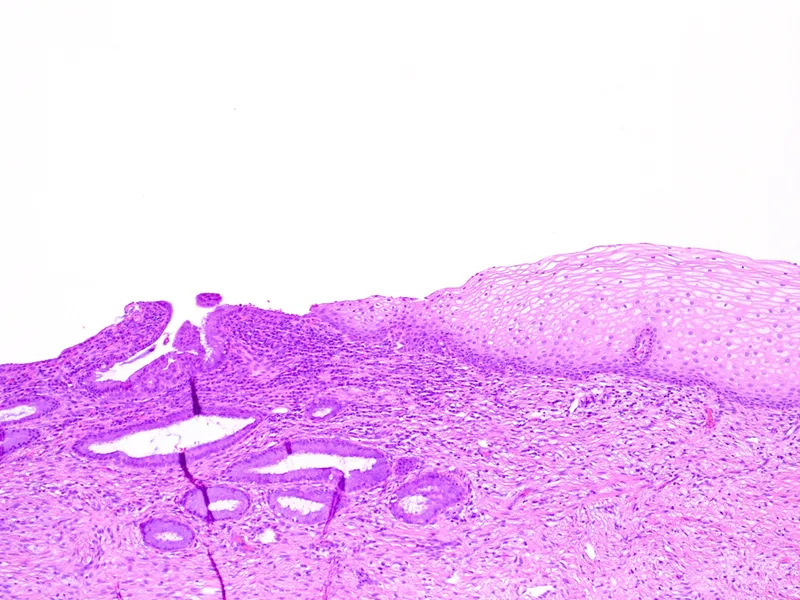

- Ectocervix: Projects into vagina; lined by stratified squamous non-keratinized epithelium.

- Endocervix (canal): Lined by simple columnar (mucinous) epithelium.

- Squamocolumnar Junction (SCJ): Original meeting point of squamous and columnar epithelia.

- Transformation Zone (TZ): Area between original and new SCJ; undergoes squamous metaplasia.

⭐ The transformation zone (TZ) is the primary site for development of cervical intraepithelial neoplasia and cervical cancer.